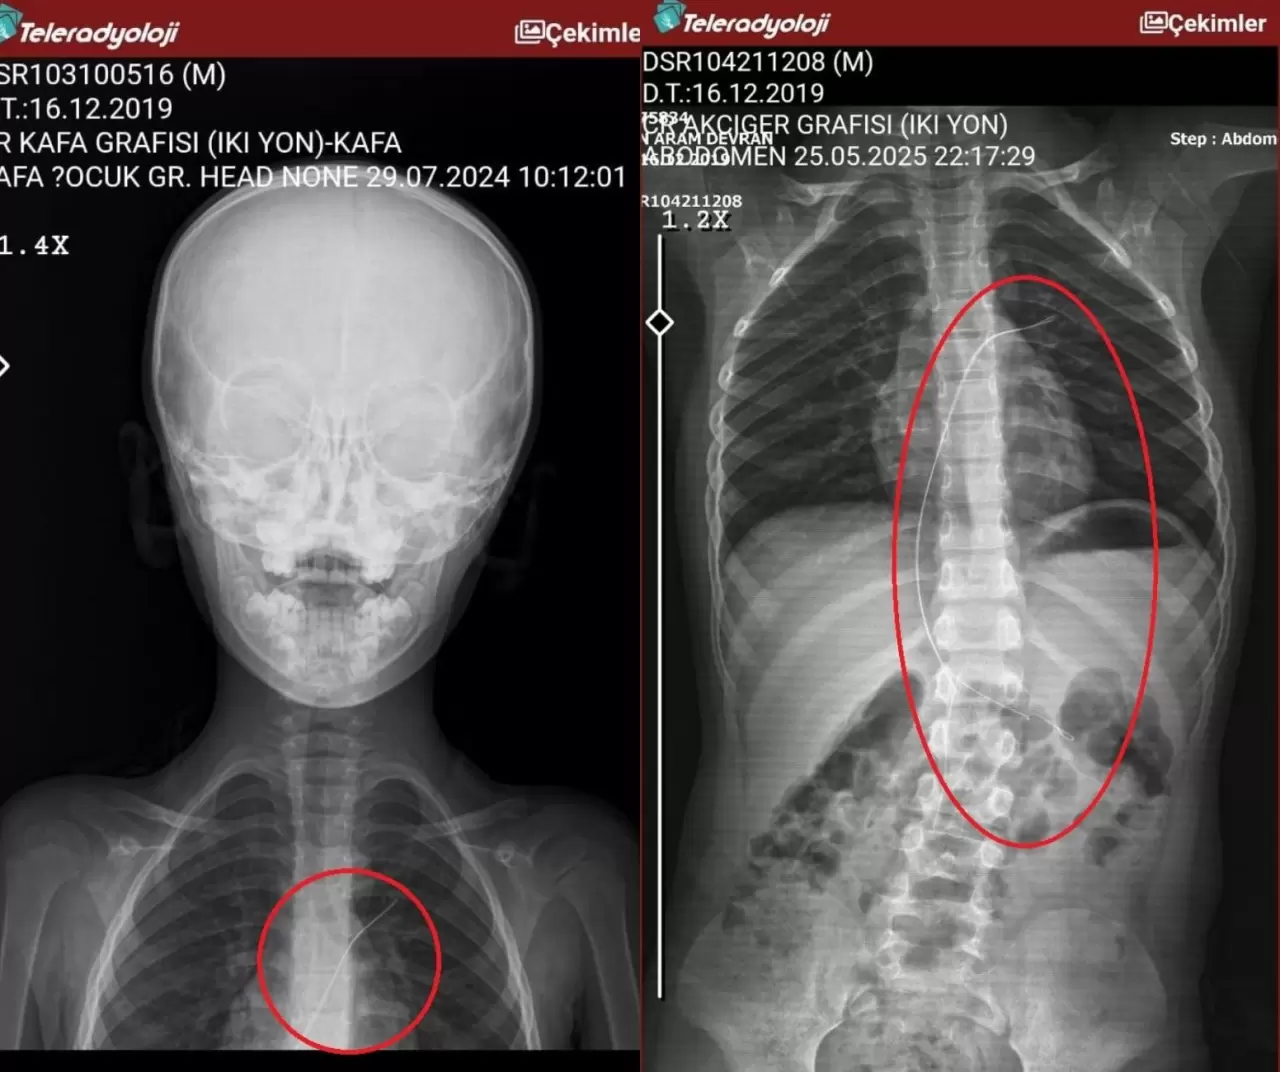

Şırnak’ta piknikte salatalık parçası yuttuktan sonra öksürük ve kusma şikayetleriyle hastaneye götürülen 6 yaşındaki Aram Devran Ötün’ün, 3 yıl önce Stevens- Johnson sendromu nedeniyle tedavi gördüğü sırada damar yoluna takılan 18 santimetrelik kateterin vücudunda unutulduğu ortaya çıktı. Öğüt, 5,5 saat süren riskli bir ameliyatla kateterden kurtuldu.

Şırnak’ta yaşayan 37 yaşındaki Semra ve 40 yaşındaki Mehmet Ötün çiftinin oğulları Aram Devran Ötün, mayıs ayında piknikteyken salatalık parçası yuttuktan sonra öksürük ve kusma şikayetleri görülünce Şırnak Devlet Hastanesi’ne götürüldü. Burada çekilen röntgen ve MR’da Aram’ın vücudunda kateter unutulduğu görüldü. Diyarbakır’daki Gazi Yaşargil Eğitim ve Araştırma Hastanesi Kadın Doğum ve Çocuk Ek Binası’na sevk edilen Aram, 5,5 saat süren riskli bir ameliyata alınarak 18 santimetre uzunluğundaki kateter çıkarıldı. Ameliyat sonrası yapılan incelemelerde kateterin kalp kapakçığına ve ciğerlerine zarar verdiği belirlendi.

“Müvekkilim Aram Devran Ötün, 2022 Eylül ayında Dicle Üniversitesi Hastanesi’nde Stevens- Johnson hastalığı nedeniyle tedavi gördü. Tedavi sırasında kendisine kateter takıldı. 18 santimetre uzunluğundadır. Bunu takarken büyük bir ihmalkarlık yapılarak vücudunda unutuldu. Mayıs ayında müvekkilim çok öksürdüğü için Şırnak Devlet Hastanesi’ne kaldırıldı. Burada yapılan tetkiklerde kateterin unutulduğu tespit edildi. Daha sonra Diyarbakır Gazi Yaşargil Kadın ve Çocuk Hastalıkları Hastanesi’ne götürüldü.“

”Çok riskli bir ameliyata alındı ve kateter çıkarıldı. Bu kateterin vücutta yol aldığı tespit edildi. İlk giriş yeri ve çıkarıldığı yer arasında çok fark var ve kalp kapakçığı ile ciğerlerine zarar verdiği tespit edildi. Müvekkillerimin hem maddi hem de manevi zararlarını karşılamak adına Dicle Üniversitesi’ne biz başvuruda bulunduk. 30 günlük cevap süresi içerisinde bize geri dönüş yapılmadı. Biz de maddi ve manevi zararların tazminat için Diyarbakır İdare Mahkemesi’ne davamızı açtık ve sorumlulardan şikayetçi olduk” dedi.

”Akşam 21.00 civarında acile götürdük. Röntgeni ve MR’ı çekildi. Tuhaf bir şey olduğunu anladık. Doktor röntgeni gösterdi. Tel kalmıştı. Çok kötü bir şekilde. Acil doktoru film çektikten sonra bize bir tel parçasını gösterdi. Bizi bekletmeden Diyarbakır’a sevkimizi verdiler. Diyarbakır Gazi Yaşargil Eğitim ve Araştırma Hastanesi Kadın Doğum ve Çocuk Ek Binası’na gittik. Çocuğun kasıklarından anjiyo yolu ile teli çıkaracaklarını ama riskli bir ameliyat olduğunu söylediler. O süreçte çocuk gerçekten sürekli yoruluyordu. İkide bir oturuyordu. ‘Anne çok yoruldum, karnım ağrıyor’ diyordu. Ben ağrı kesiciler ile geçiştirmeye çalışıyordum. Bu telin 3 yıl boyunca çocuğumda kaldığını öğrendim. Ailece yıkıldık” diye konuştu.